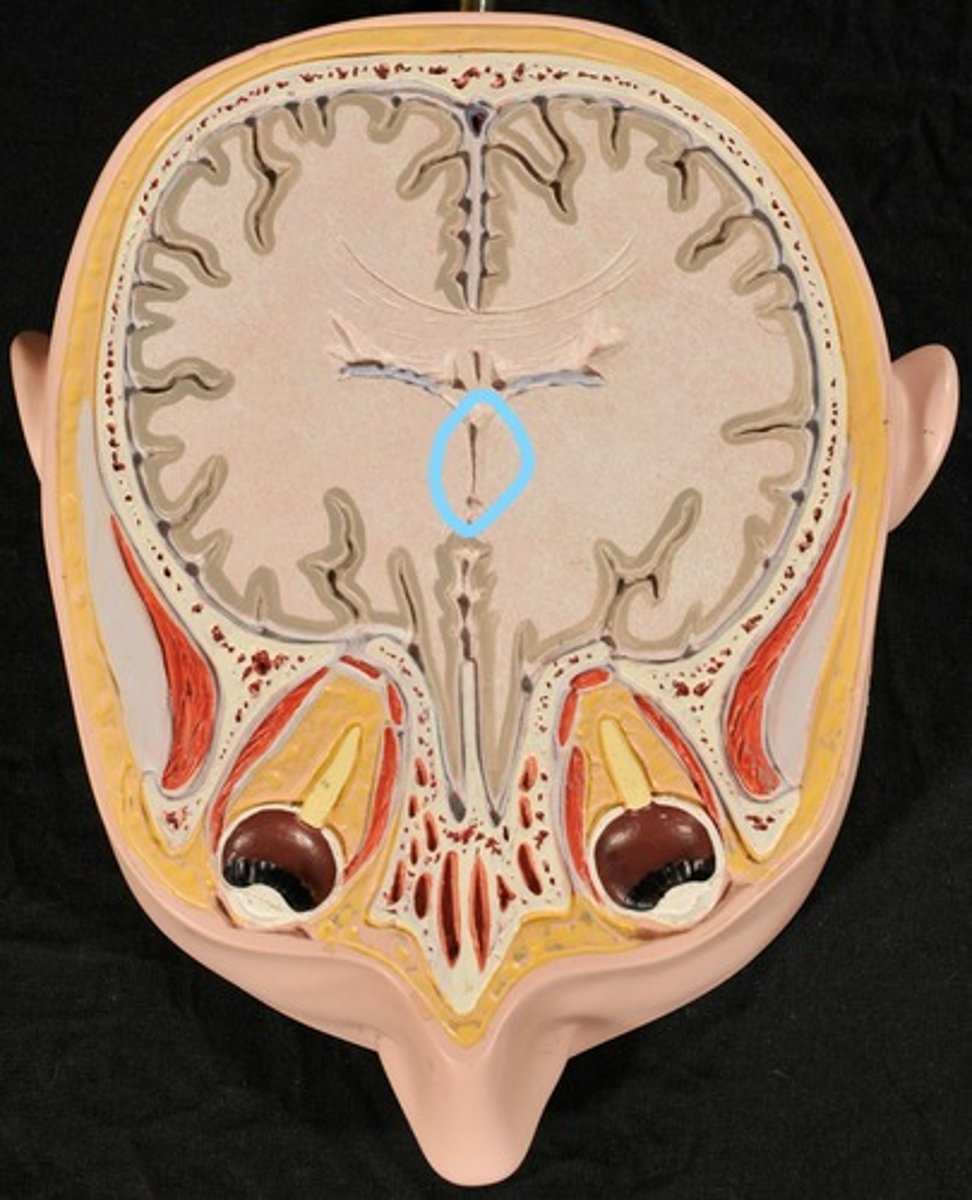

Third Ventricle

Cerebral Aqueduct

Third Ventricle (Slice 2)